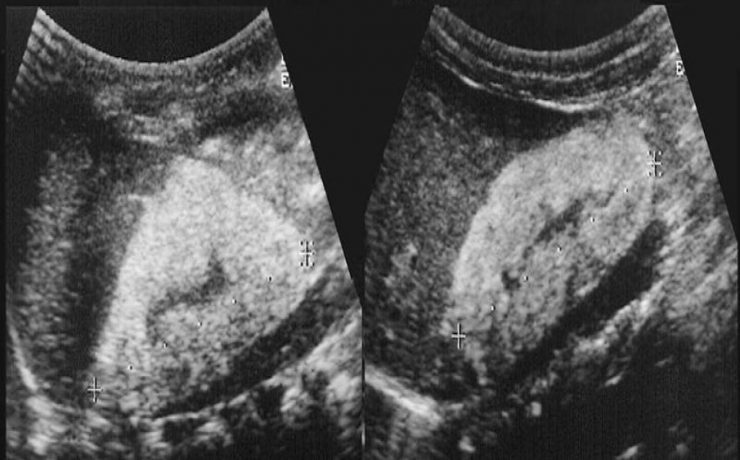

Valoración ecográfica de la patología ovárica

Existen alteraciones ováricas valorables por ecografía tratándose generalmente de alteraciones foliculares las cuales se presentan clínicamente como defectos en la maduración además del número de los mismos. Ecográficamente se diferencia el tamaño, el grosor capsular y su estroma puede estar aumentado e hiperecogénico. Otra patología son los quistes que